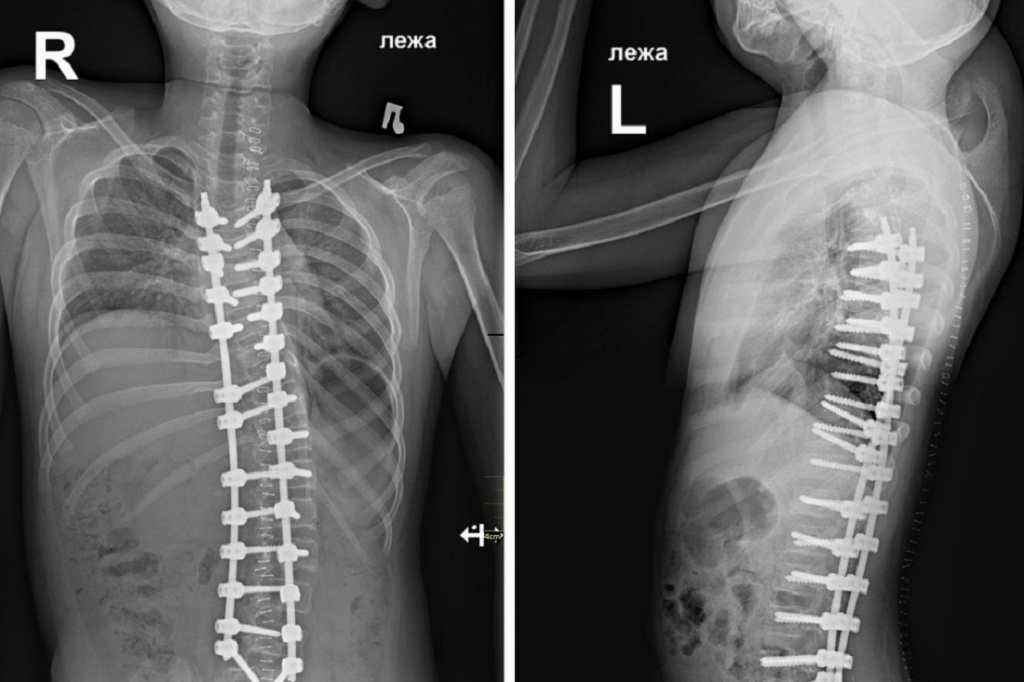

Состояние пациента после операции. Фото: Новосибирский НИИТО имени Я. Л. Цивьяна

Слаженная работа врачей позволила провести вмешательство за четыре часа — бригада выполнила тотальную фиксацию позвоночника от грудного Th3-позвонка до поясничного L4-позвонка, установила ребёнку специальную металлоконструкцию.

В институте отмечают, что операция прошла штатно, искривление удалось скорректировать до 32 градусов. Визуально оно всё ещё может быть заметно, но первостепенной задачей специалистов был не столько косметический эффект, сколько обеспечение комфортной жизни пациенту.